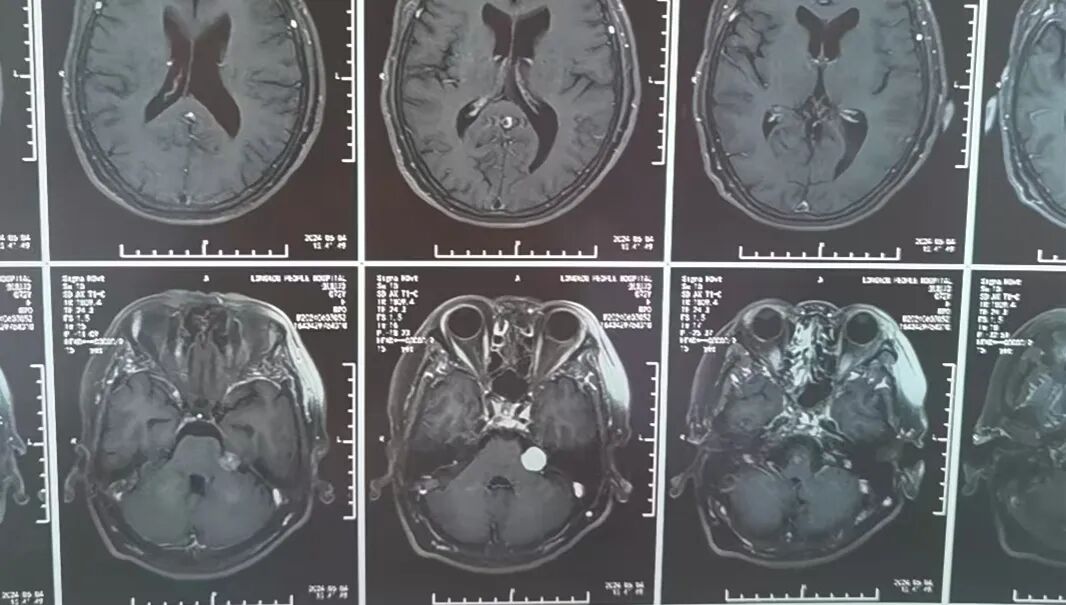

原来,李先生的母亲今年72岁,家住龙口市,一年前在当地医院查体,发现左侧桥小脑角区占位病变,诊断为“听神经瘤”,肿瘤小于2cm,医生建议观察1年后复查。1月前,老人出现了左耳听力下降的临床症状,复查颅脑核磁发现肿瘤有明显生长!

因肿瘤起源于神经的鞘膜,压迫面听神经,术中保留面听神经功能显得尤为重要。手术由耿素民教授亲自主刀,在我院神经外科团队的配合下,术中应用显微镜和神经内镜双镜联合辅助,不磨除内听道骨质便成功将肿瘤全部切除,并完好保留了面听神经功能。